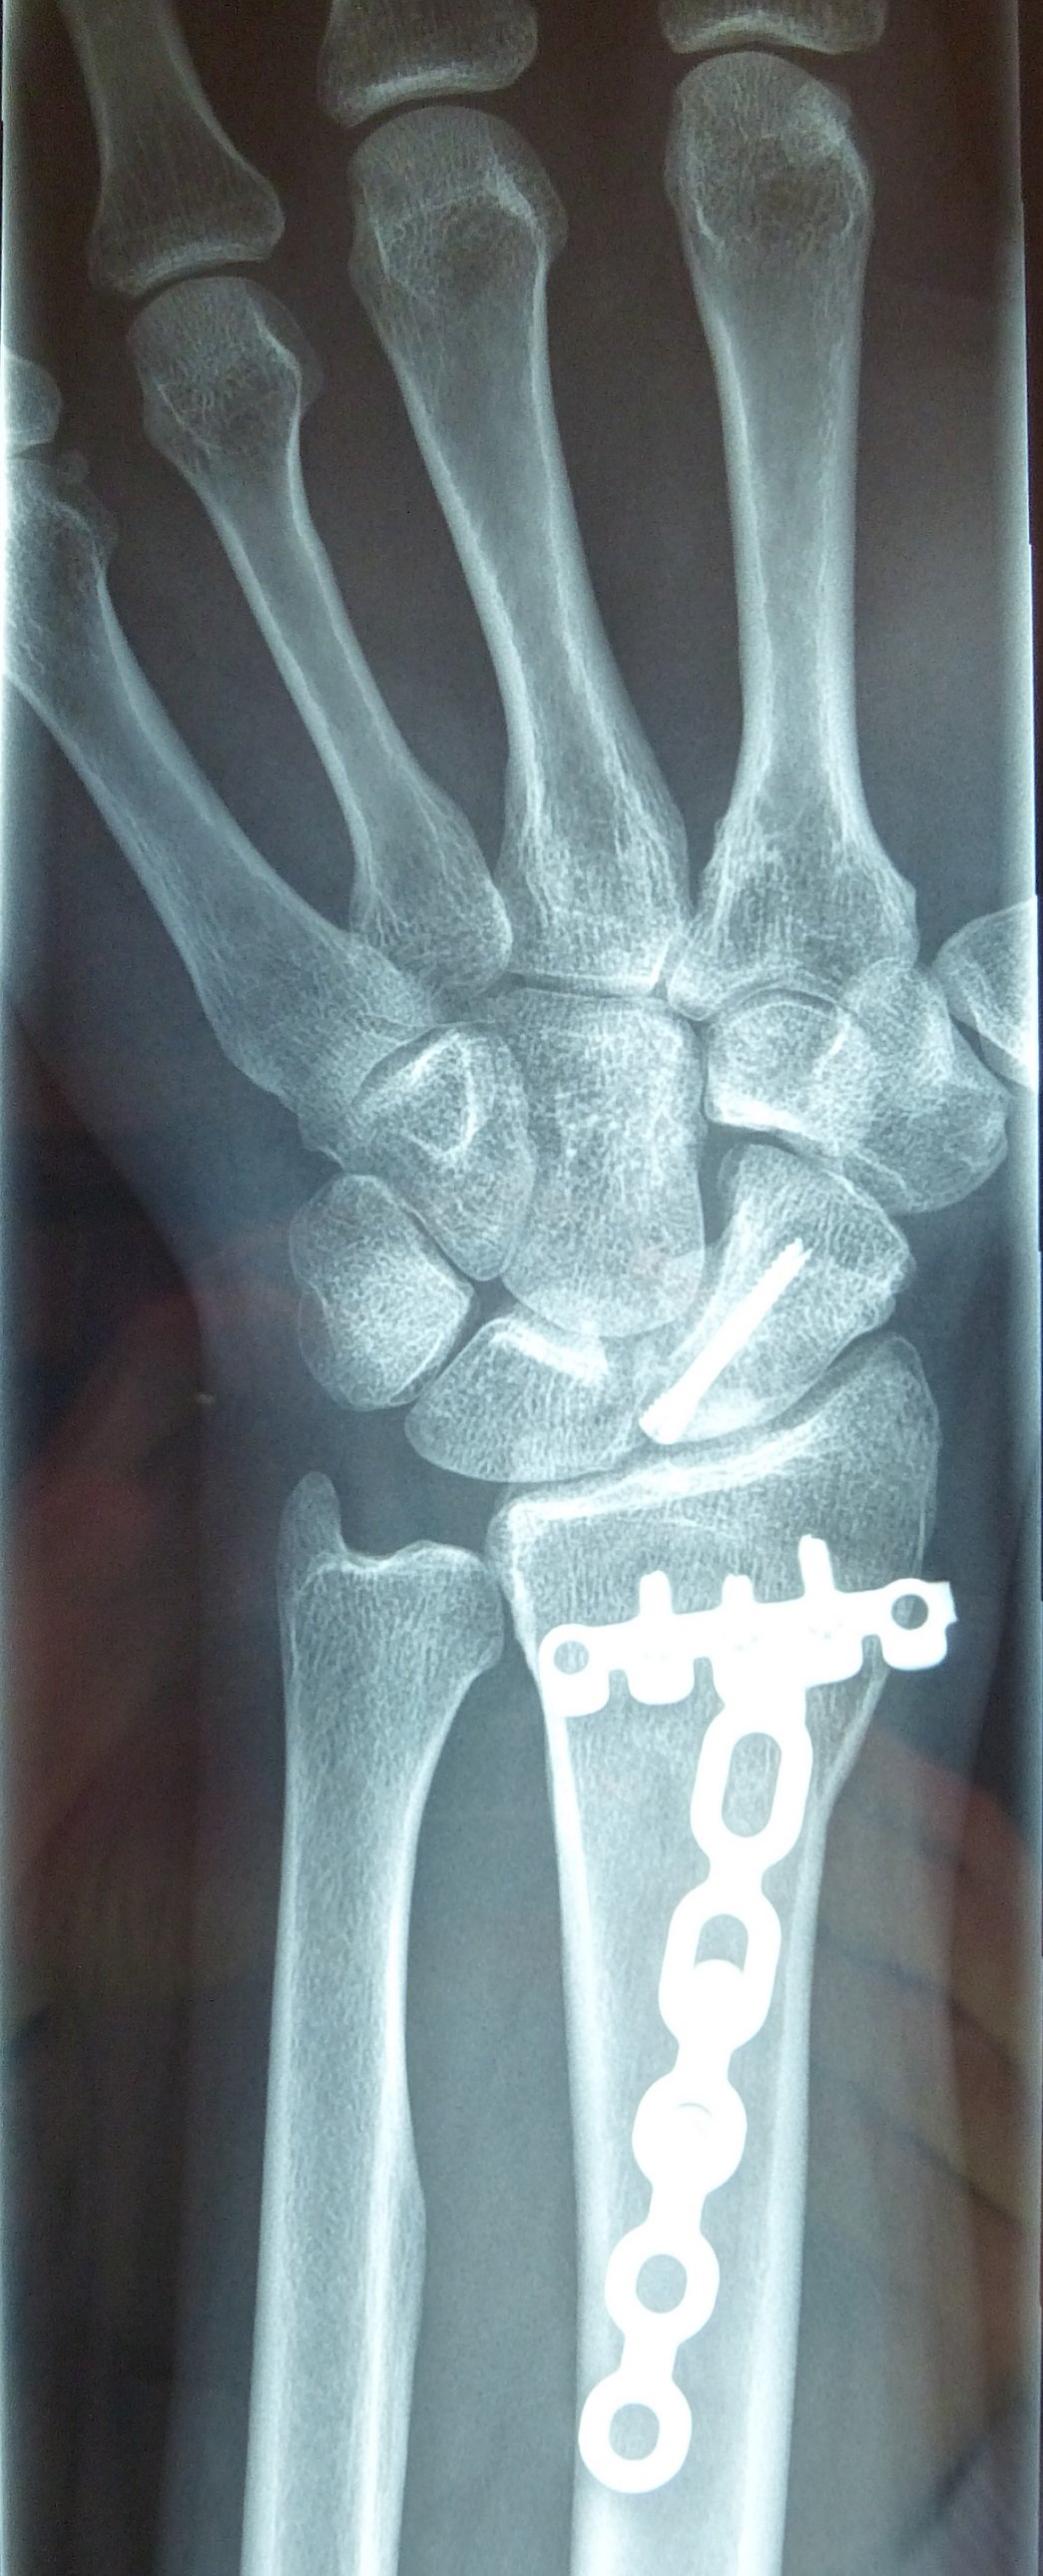

Η αντιμετώπιση της ψευδάρθρωσης του σκαφοειδούς είναι πάντοτε χειρουργική. Με ραχιαία ή παλαμιαία προσπέλαση αποκαθίσταται ο άξονας του σκαφοειδούς και σταθεροποιείται το σκαφοειδές με ειδική βίδα ή βελόνες, με παράλληλη τοποθέτηση οστικών μοσχευμάτων. Μπορεί επιπλέον να γίνει και οστεοτομία κλειστής σφήνας του περιφερικού άκρου της κερκίδος. Στις περιπτώσεις άσηπτης νέκρωσης το μόσχευμα πρέπει να είναι αγγειούμενο – για να προσδώσει αιμάτωση στο νεκρωμένο κεντρικό τμήμα – και λαμβάνεται με μικροχειρουργικές τεχνικές από το περιφερικό τμήμα της κερκίδος ή από άλλα τμήματα του σώματος

Προεγχειρητικά

Μετεγχειρητικά 1

Μετεγχειρητικά 2

Περίπτωση 2: Μετεγχειρητικά 1

Περίπτωση 2: Μετεγχειρητικά 2